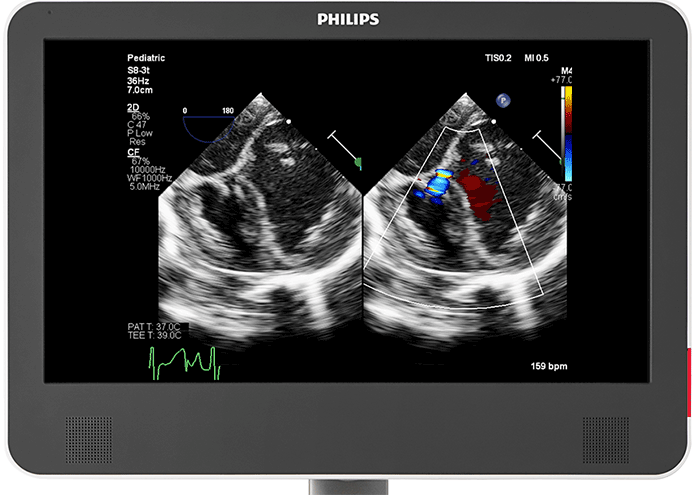

小児心臓用 PureWave トランスジューサ PureWave S9-2 トランスジューサは、シングルクリスタルテクノロジーにより、詳細で優れたコントラスト分解能を有し、さらに超広帯域幅による優れたペネトレーションを実現します。その結果、より深い部位においても詳細な組織情報を低ノイズで取得できます。実際、新型 EPIQ CVx Transcend を見た小児患者担当臨床医の 92%⁶が、新型 PureWave S9-2 トランスジューサはより優れた 2D モードのイメージングを可能にすると回答しました²。

冠動脈の容易かつ迅速な評価 フィリップス EPIQ CVx Transcend のワンボタン式コロナリーサブモード(多くのセクタトランスジューサに搭載)を搭載した新型 EPIQ CVx Transcend を見た小児患者担当臨床医の 92%6が、川崎病、冠動脈異常、冠動脈瘻の病状検出において、現在使用しているシステムよりも EPIQ CVx Transcend のコロナリーサブモードの方が優れていると回答しました2。

鮮明な画像表示 EPIQ CVx Transcend には、22 インチの第二世代有機 EL モニタが搭載されています。180° の視野角を提供し、ダイナミックレンジおよび色範囲も従来製品より拡大しました。さらに、MaxVue による全画面表示により、画像サイズは解像度を犠牲にすることなく従来型超音波画像と比較して 38% 大きくなっています。その結果、並列比較、カラー比較、xPlane、Live 3D、MPRs、負荷エコー画像の機能が強化されました。

小さな患者のための 2D TEE フィリップスのマルチプレーン MicroTEE S8-3t は細径シャフトを実現しており、重要な心臓カテーテル術や外科手術中における 2.5kg 程度の極めて小さな乳児のイメージング、および新生児の高性能リアルタイムイメージングが可能です。